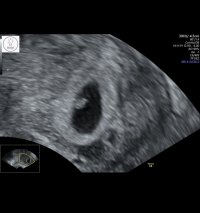

Hun sa og at det så veldig ut som en jente basert på hvor tydelig det viste, men selvfølgelig er det tidlig enda. Hun pleide normalt sett ikke uttale seg så tidlig men her syns hun det var greit å se. Vi har en av hver så begge deler er like kjekt, men hva tror dere basert på NUB?Jeg ville også sagt jente!Privat ul i dag før ferien med fosterdiagnostikk 11+4. Ble målt til rett under 5 cm, veldig fine mål på nakkefold, og ellers tipp topp anatomi og hjerterytme. Alt var som det skulleHun sa og at det så veldig ut som en jente basert på hvor tydelig det viste, men selvfølgelig er det tidlig enda. Hun pleide normalt sett ikke uttale seg så tidlig men her syns hun det var greit å se. Vi har en av hver så begge deler er like kjekt, men hva tror dere basert på NUB?

Var dette ordinær tidlig ultralyd?11+2![]()